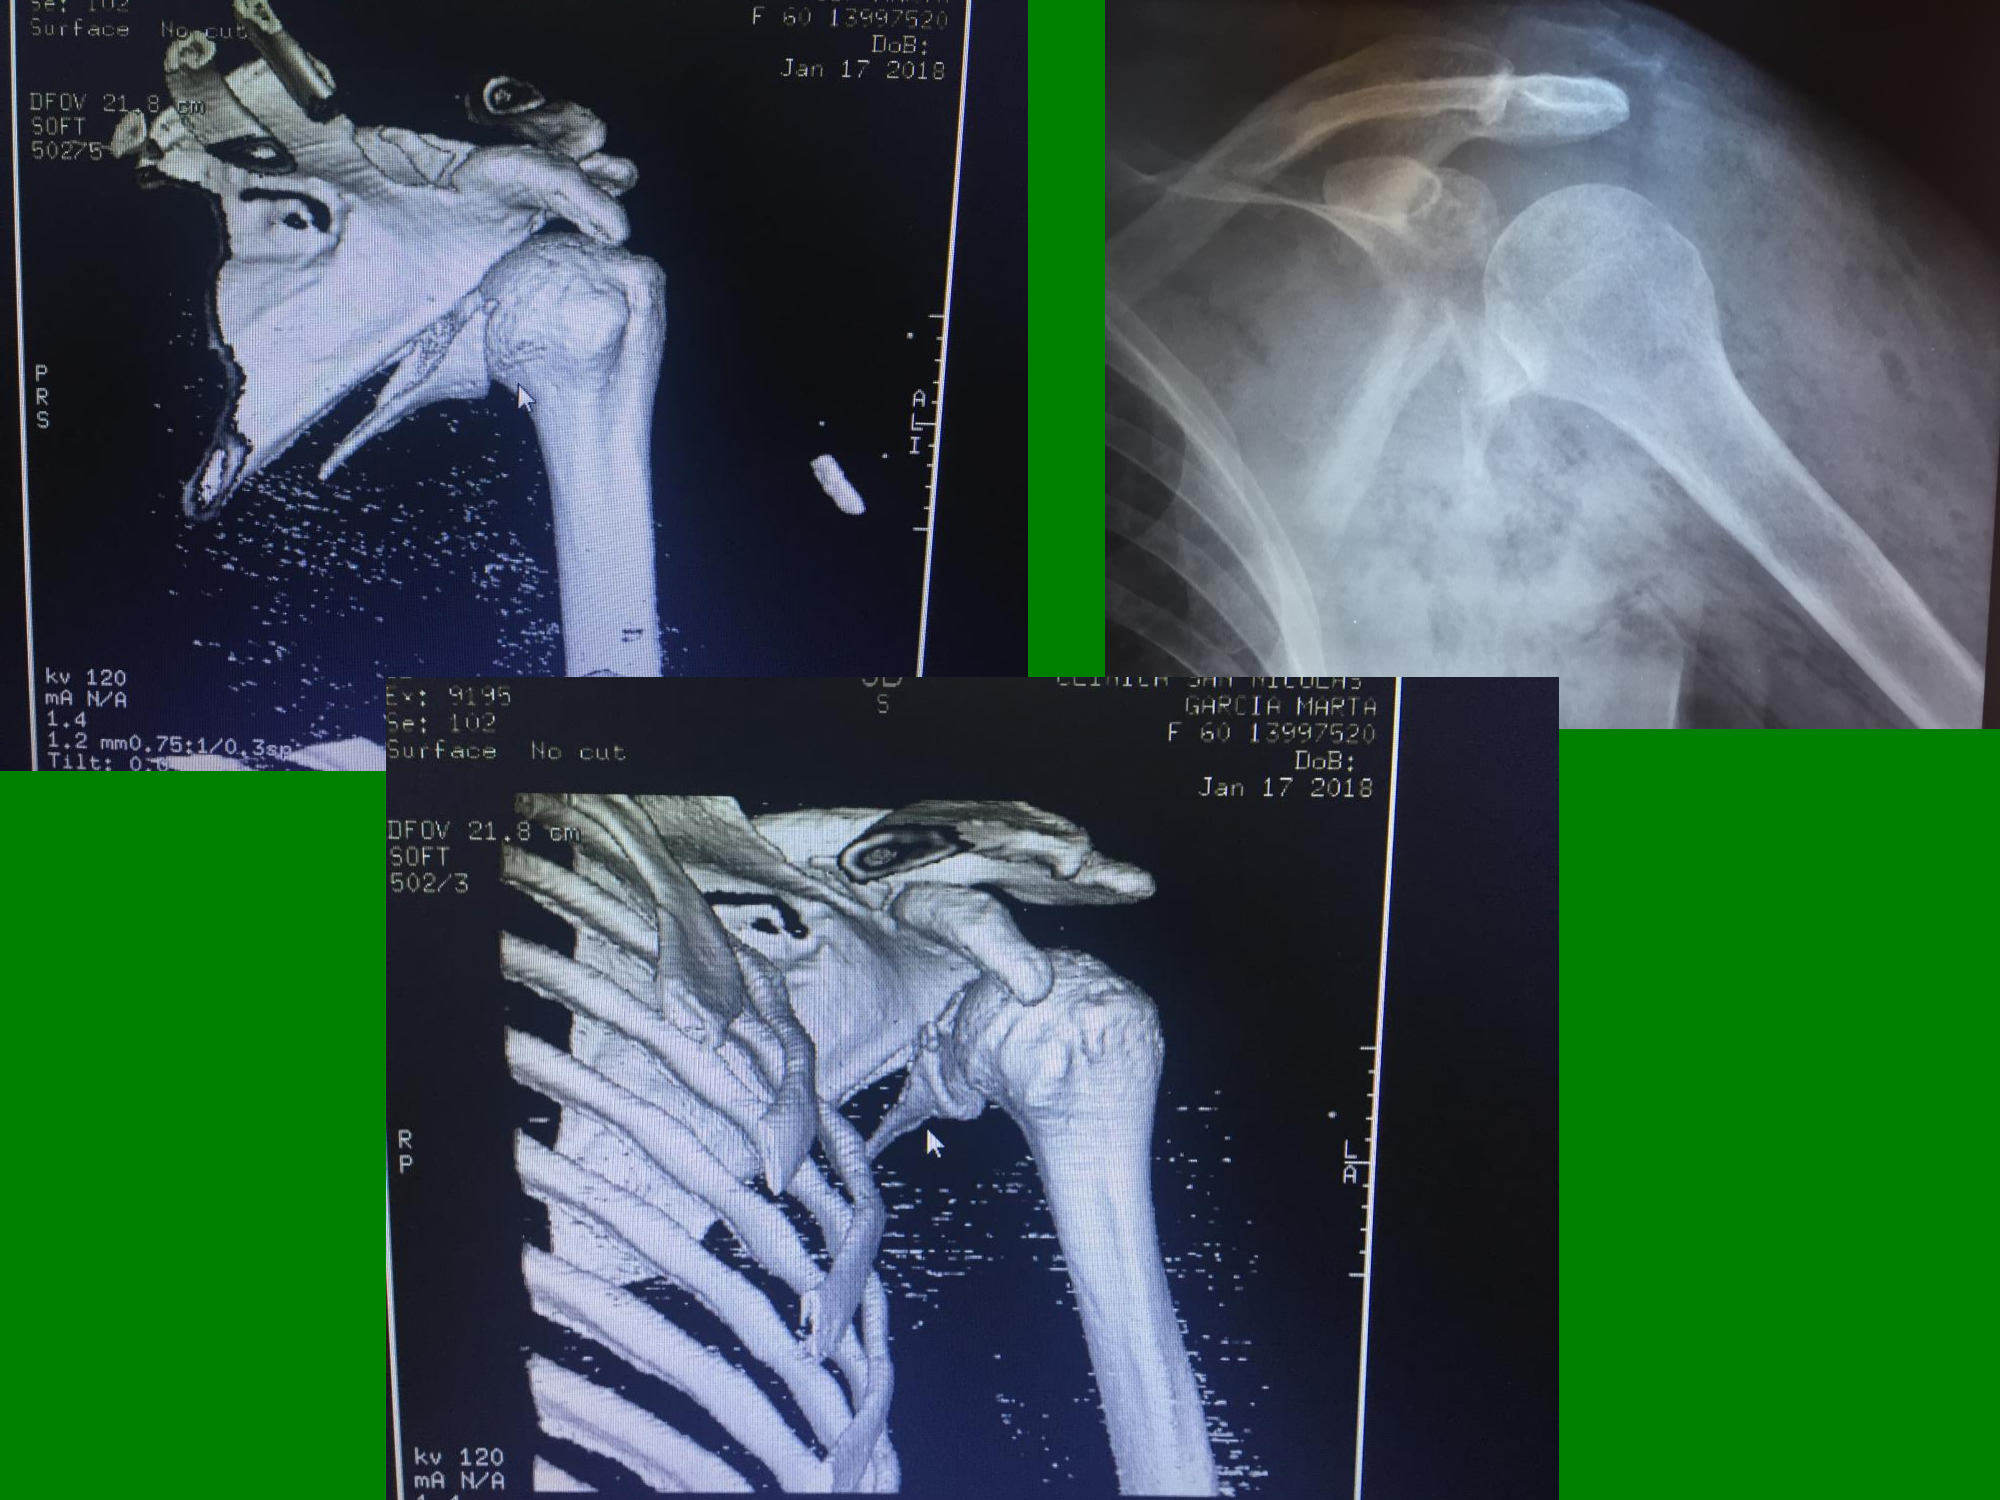

06_“Fractura de glena como complicación de movilización bajo anestesia en paciente con hombro congelado. Reporte de un caso”

Dres. Esteban Suárez – Iván Benedetto (San Nicolás, Buenos Aires).